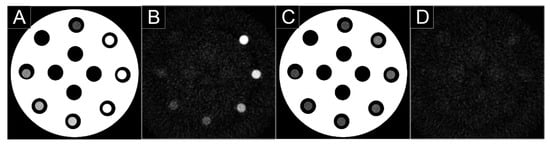

- Si-Mohamed, S.A.; Greffier, J.; Miailhes, J.; Boccalini, S.; Rodesch, P.A.; Vuillod, A.; van der Werf, N.R.; Dabli, D.; Racine, D.; Rotzinger, D.; et al. Comparison of image quality between spectral photon-counting CT and dual-layer CT for the evaluation of lung nodules: A phantom study. Eur. Rad. 2021, in press. [Google Scholar] [CrossRef] [PubMed]